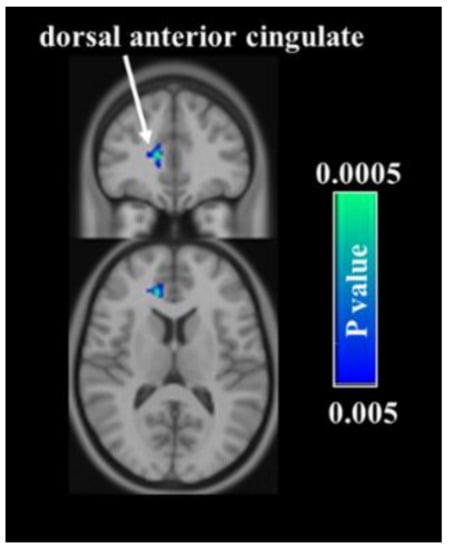

3.2. CBF Voxelwise Analyses

- Russo, J.F.; Sheth, S.A. Deep brain stimulation of the dorsal anterior cingulate cortex for the treatment of chronic neuropathic pain. Neurosurg. Focus 2015, 38, E11. [Google Scholar] [CrossRef]

- Devinsky, O.; Morrell, M.J.; Vogt, B.A. Contributions of anterior cingulate cortex to behaviour. Brain 1995, 118, 279–306. [Google Scholar] [CrossRef]